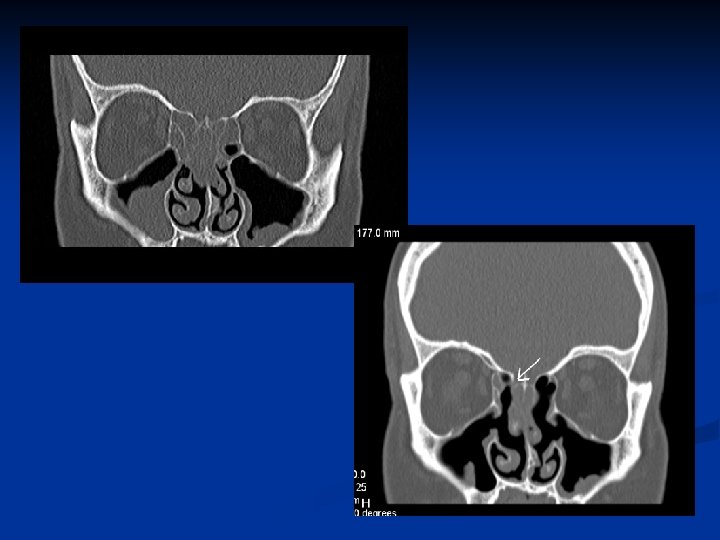

Kazuistika 2. n n n 48 ročný pacient Obojstranná FESS operácia v CA pre nosovú polypózu Predoperačne lokálne a celkovo kortikoidy 2. pooperačný deň udáva výtok čírej tekutiny z pravej nosovej dierky Na základe anamnézy, endoskopického vyš. a HRCT diagnostikovaná iatrogénne spôsobená rinolikvorea vpravo v oblasti lamela lateralis, indikovaná duraplastika vpravo

Kazuistika 3. n n n 61 - ročná pacientka FESS operácia vpravo pre nosovú polypózu s postihnutím pravej maxilárnej, čelovej dutiny a predných ethmoidov Peroperačne odstránený zo stredného nosového priechodu cystický polypózny útvar, dutiny vyplnené hlienohnisom Pacientka týždeň po operácii pri amb. kontrole udáva výtok čírej tekutiny z pravej nos. dierky Na základe anamnézy, endoskopického nálezu a HRCT diag. rinolikvorea v oblasti nazofrontálneho vývodu a stropu ethmoidov, indikovaná duraplastika vpravo Stav hodnotíme ako meningokélu s následnou rinolikvoreou